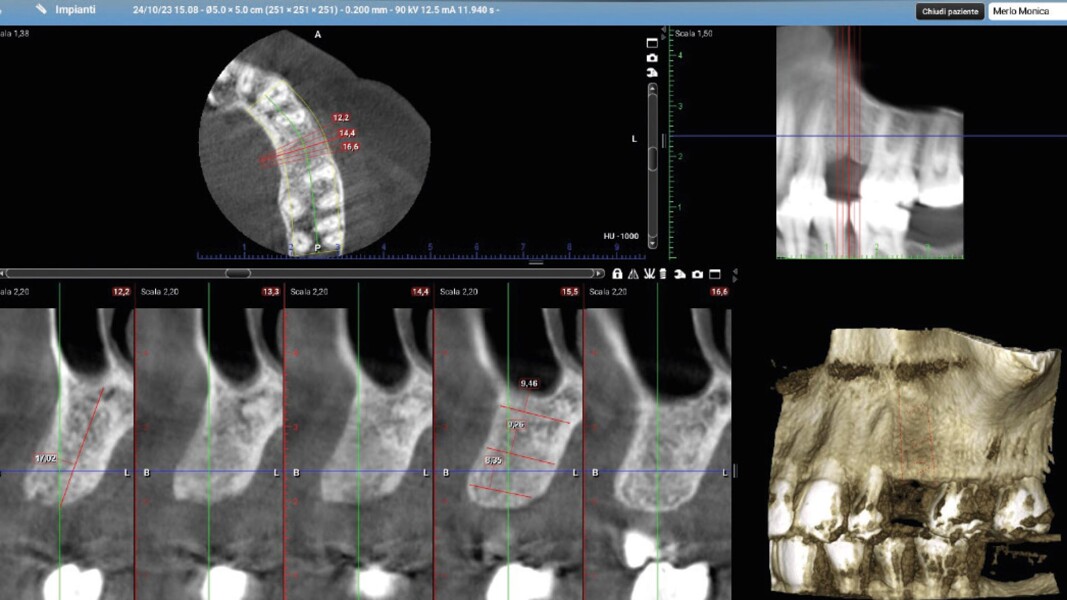

Una paziente di 50 anni presentava un premolare superiore non recuperabile. Dopo CBCT preoperatoria (T0) (Fig. 1), si è proceduto all’estrazione atraumatica e alla gestione dell’alveolo mediante posizionamento vestibolare di una membrana corticale eterologa (Lamina fine 0,7 mm, 35 × 15 mm, OsteoBiol) e riempimento con spugne di collagene (Figg. 2, 3). Sono stati applicati punti di sutura in nylon non riassorbibile 4/0. Dopo sei mesi di guarigione, una nuova CBCT (T1) ha consentito la valutazione della qualità ossea. Per la fase implantare è stato eseguito un lembo secondo la tecnica del roll flap, con preservazione delle papille interdentali e aumento del tessuto cheratinizzato (Fig. 4). È stato inserito un impianto JD Evolution Plus (4,3 × 11,5 mm) ottenendo un’eccellente stabilità primaria. Durante la chirurgia è stato prelevato un campione osseo per analisi istologica (Fig. 5).  Il lembo è stato suturato con nylon 4/0 intorno all’abutment di guarigione. Dopo due mesi, la paziente è stata riabilitata con una corona monolitica in zirconia realizzata da impronta digitale intraorale (Fig. 6).

Il protocollo chirurgico ha seguito i principi della tecnica LAR, prevedendo una gestione stratificata dei materiali rigenerativi al fine di ottenere stabilità volumetrica e controllo biologico del sito post-estrattivo. La membrana ossea eterologa ha fornito un supporto rigido e stabile per la rigenerazione ossea e il mantenimento dei contorni alveolari. Le spugne di collagene sono state scelte per la loro biocompatibilità e capacità di favorire emostasi e rigenerazione tissutale. Le misurazioni dello spessore osseo sono state effettuate su CBCT a T0 e T1 in tre punti:

1. porzione coronale;

2. terzo medio;

3. terzo apicale.

L’analisi CBCT ha evidenziato un mantenimento del volume osseo con valori comparabili tra T0 e T1.

• T0: larghezza 9,22 mm, altezza 17,12 mm;

• T1: larghezza 9,46 mm, altezza 17,02 mm.